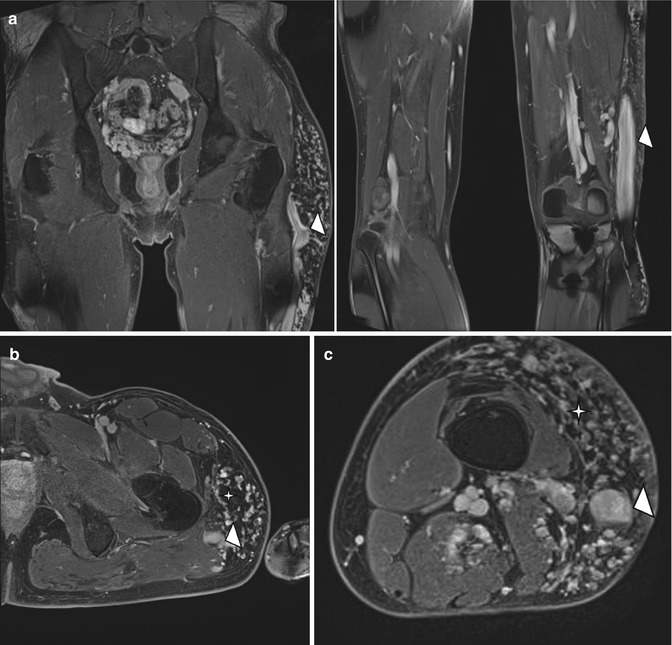

Klippel-Trenaunay syndrome in a 30-year-old boy. (a) Coronal T2-weighted MR image with fat suppression. (b, c) Axial T2-weighted MR images with fat suppression of the pelvis and thigh. (a–c) There is hemihypertrophy of left lower extremity with extensive subcutaneous (star) and intramuscular venous malformations. Note the characteristic abnormal sapheneous vein (arrowhead in c)